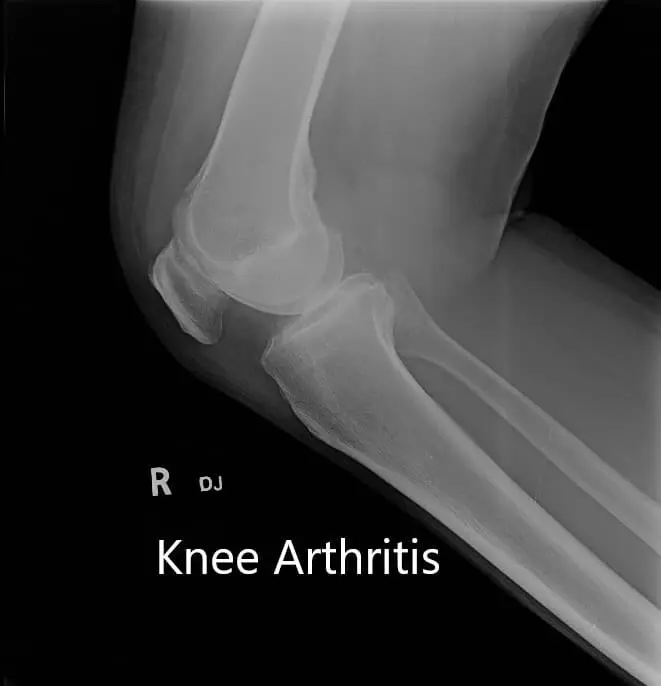

Imaging studies revealed tricompartmental osteoarthritis with degenerative changes. She was advised custom right total knee replacement considering her examination and needs. A preoperative CT was to be obtained a few weeks prior to surgery.

Preoperative X-ray showing AP and lateral view of the right knee joint, and skyline view of both the knee joints.